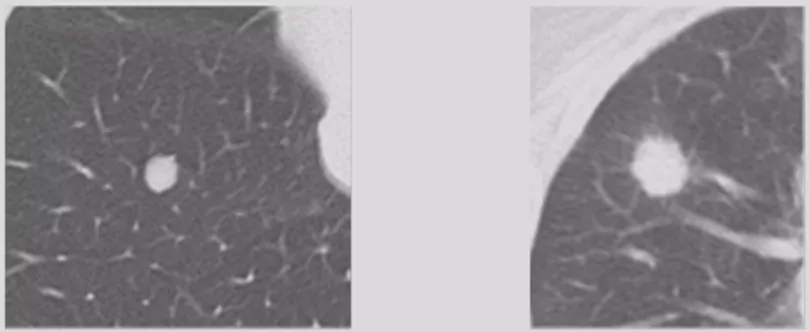

光滑或粗糙

边缘光滑多为良性病变,但仍有1/4-1/3的边缘光滑结节为恶性病变,因此不能作为排除恶性的标准(左图)。边缘粗糙表明肿瘤沿肺泡壁侵袭,多见于肺腺癌(右图)。

毛刺征

短毛刺(左)长毛刺(右)

毛刺又分长毛刺和短毛刺,短毛刺为肿瘤细胞向邻近肺实浸润时,支气管血管鞘或局部淋巴管阻挡,或肿瘤的促结缔组织生成反应的纤维带,其预测恶性的阳性预测值88%-94%。长毛刺是炎性的表现,良性病变边缘亦可见毛刺,多较长、柔软,常由增生的纤维结缔组织所形成,如炎性假瘤和结核球的毛刺为纤维包膜外增厚的小叶间隔。但是长度多少叫做长毛刺,多短叫短毛刺,没有明确定论,但是总体来说毛刺还是有一定规律的。